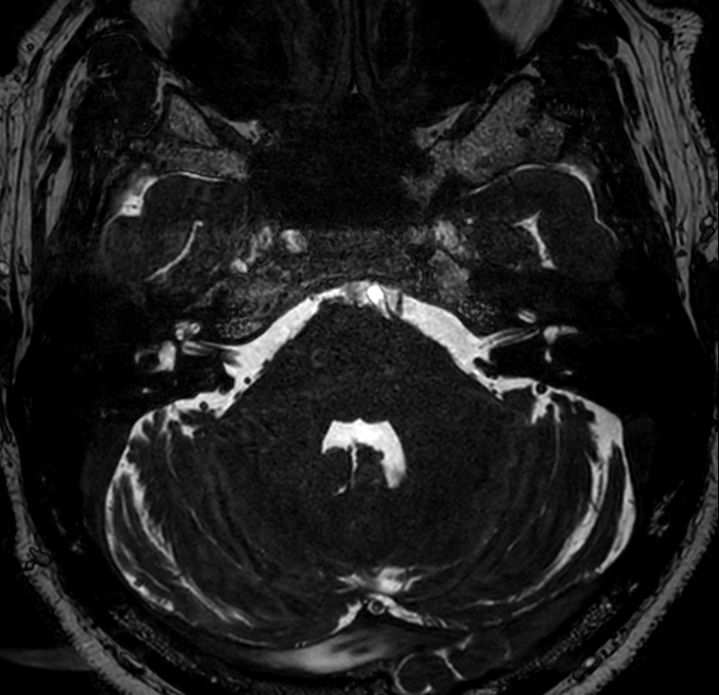

Axial bFFE XD